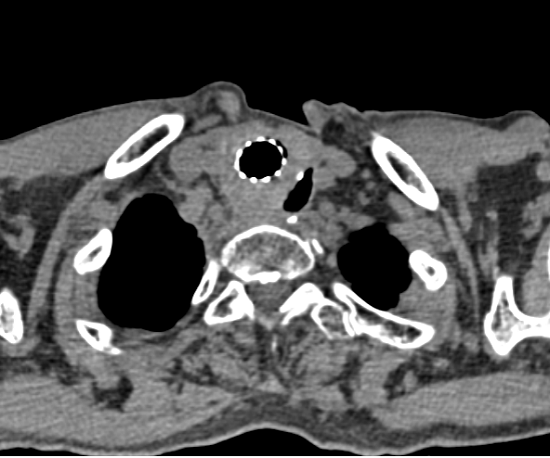

70岁的患者于XX,自2018年确诊食管恶性肿瘤以来,与病魔展开了一场持久的拉锯战。他先后接受了手术、化疗、放疗乃至针对复发的多次积极治疗,就在病情数次得到控制之后,2025年6月,治疗迎来了最为严峻的挑战——患者出现典型呛咳,经增强CT检查,确诊为食管癌治疗过程中极为棘手的并发症——食管气管瘘。

食管气管瘘导致唾液和食物进入气道,极易引发严重肺部感染和营养不良,传统治疗难度大、预后差。面对挑战,肿瘤内科一区主任张秀亮高度重视,立即启动多学科会诊(MDT)机制,联合影像科、消化内科、胸心外科、呼吸与危重症医学科、营养科等专家进行深入讨论。专家团队全面评估了患者病情,最终确立了以内镜下食管支架置入术为核心的综合治疗方案。